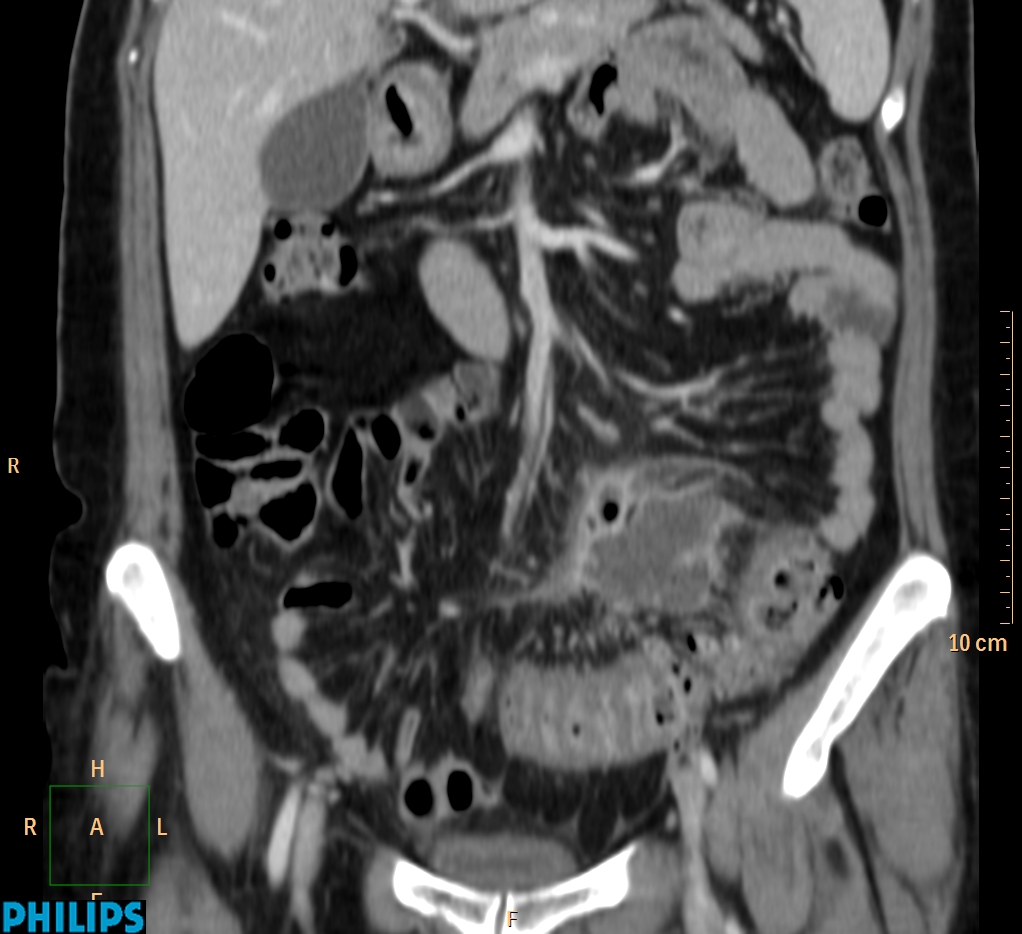

ΕΚΚΟΛΠΩΜΑΤΑ ΠΑΧΕΟΣ ΕΝΤΕΡΟΥ Posted by ΙΠΠΟΚΡΑΤΕΙΟ ΙΩΑΝΝΙΝΩΝ | Dec 16, 2020 | ΠΕΠΤΙΚΟ | 0 ΚΛΙΝΙΚΑ ΣΤΟΙΧΕΙΑ – ΙΣΤΟΡΙΚΟ υποτροπιάζοντες επαναλαμβανόμενοι πυρετοί κυρίως απογευματινές ώρες ΕΡΓΑΣΤΗΡΙΑΚΟΣ ΕΛΕΓΧΟΣ ΑΠΕΙΚΟΝΙΣΤΙΚΟΣ ΕΛΕΓΧΟΣ διακρίνονται τα αποστήματα στην ελάσσονα πύελο, καθώς και εκκολπώματα με εικόνα πάχυνσης του τοιχώματος του σιγμοειδούς ΣΥΖΗΤΗΣΗ